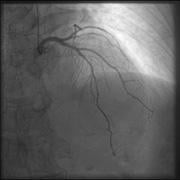

The top image is enhanced using GOPView iRVUltra. The bottom is the original image.

GOPView iRVUltra is a real-time image enhancement filter. The company’s algorithm can define the movements between the images, frame by frame, pixel by pixel, to find structures and orientation for interventional procedures in real-time and without time gaps.

“Interventional radiologists always look to strike an ideal balance between the required image quality and the radiation dose for any given procedure,” Tollstadius said. “As a result, they rely heavily on the newest advancements in image quality enhancement and dose reduction technologies. Generally, it takes an increased dose to enhance the image quality. With the GOPView iRVUltra, radiologists no longer have to compromise, as superior image quality can be achieved despite low-dose images.”